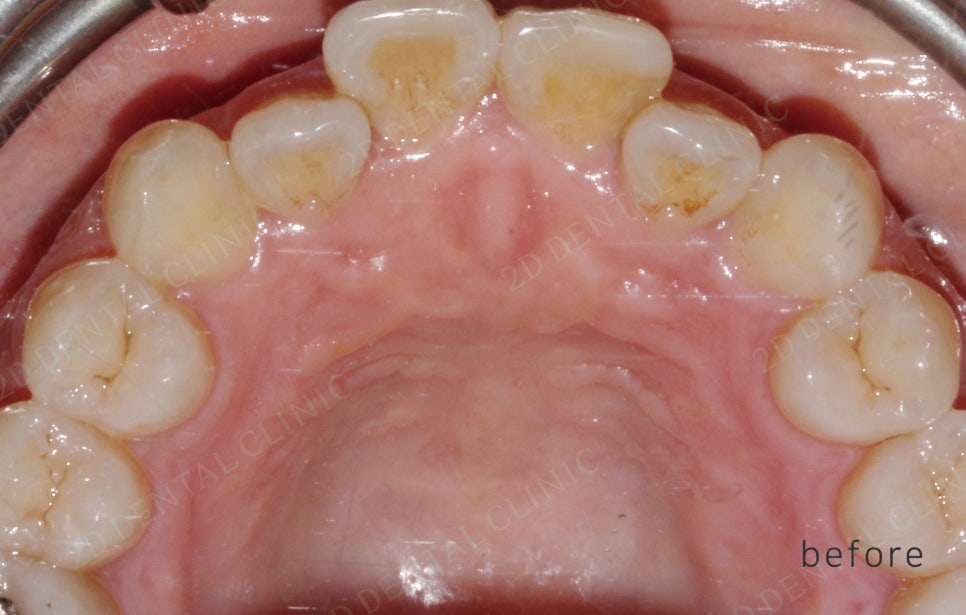

<교정 전/후 >

2D(투디)교정 앞니덧니,반대교합 치아교정

191일(약 6개월)후 투디교정 완료.

전,후 사진만 봐도 치아 배열이 잘

정돈된게 보이시나요!?